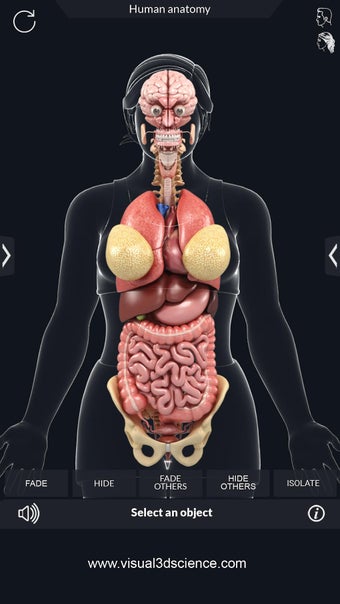

My Organs Anatomy es una aplicación de anatomía 3D gratuita desarrollada por Visual 3D Science para usuarios de Android. Esta aplicación proporciona un modelo 3D altamente realista de los órganos humanos que se puede girar 360°, acercar y alejar, y ver desde cualquier ángulo. La aplicación está diseñada para proporcionar una mirada detallada a la anatomía de los órganos humanos y ofrece varias características para ayudar a los usuarios a explorar y aprender.

La interfaz fácil de usar de My Organs Anatomy permite una navegación sencilla, lo que facilita la selección, rayos X, ocultación y visualización de órganos individuales. La aplicación también incluye un modo de animación, opciones de búsqueda y un panel de información que proporciona información relacionada. Además, la aplicación ofrece pronunciación de audio para todos los términos anatómicos, e incluso los usuarios pueden dibujar o escribir en la pantalla y compartir capturas de pantalla.

En general, My Organs Anatomy es una gran aplicación para estudiantes de medicina y cualquier persona que quiera explorar la anatomía de los órganos humanos en detalle. Con sus gráficos de alta calidad y numerosas características, esta aplicación proporciona una excelente experiencia de aprendizaje para los usuarios.